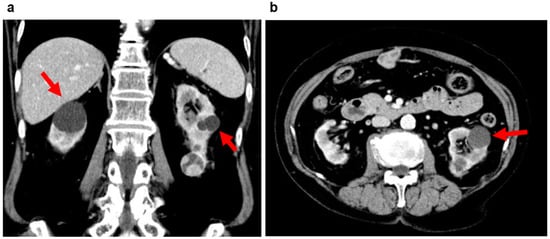

2.2. Acquired Cystic Kidney Disease (ACKD)